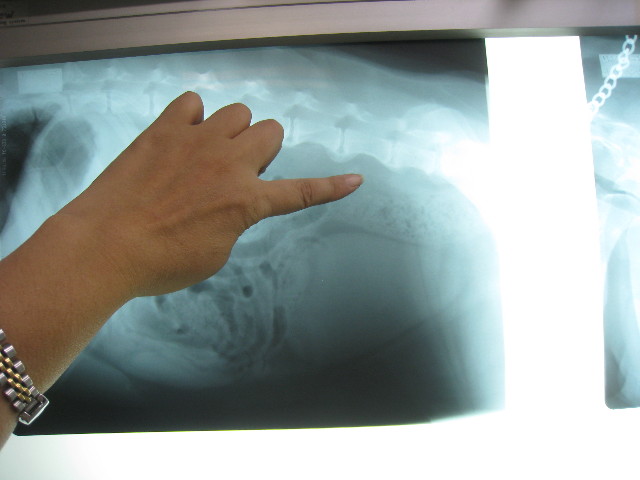

腰回りに通じるリンパが腫れていないかレントゲンを撮ってもらって検査。

指先辺り一帯が、腰回りに通じるリンパらしいけど、腫れたりの異常なし(^o^)v

ということで今のところ肛門嚢腺癌の転移や再発の徴候はなし(*゚Ω゚)/ウィッス!!

変形性脊椎症もけっこうひどくて下はいくつもブリッジになってるよね。

ブリッジになると神経には当たらないから直接の痛みは少ないけど、柔軟性がなくなって骨の動きが悪くなるからそれはそれで負担なんだって。

こちらは肺。

過去のフィラリアの影響などであいかわらず白っぽいけど、前回(7月2日)と変わっていないので大丈夫♪

左が7月2日。右が8月25日。